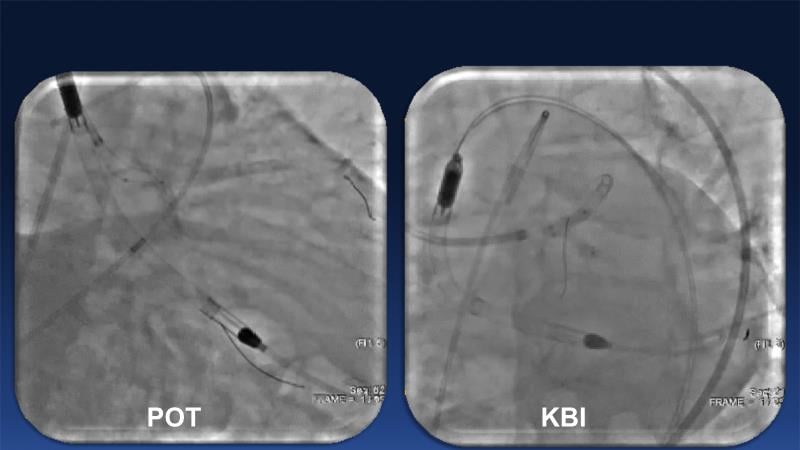

Over the last five years, we have learned that there is a new tool for treating calcium, the greatest enemy of interventional cardiology, which can take various forms: intravascular lithotripsy. In this session, look at how to master this technique in different scenarios, from eccentric calcified lesions to left main bifurcations.

- To learn how to safely utilise IVL in left main bifurcations